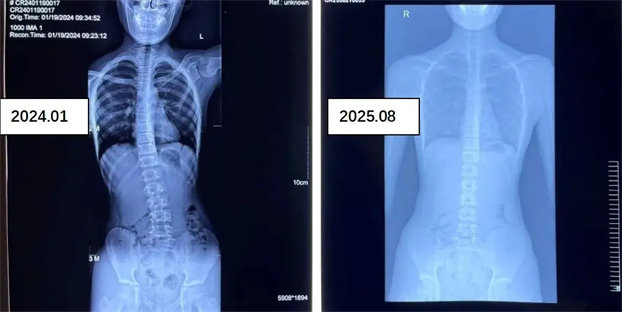

参加康复医学科脊柱侧弯训练营青少年前后对比照

影像学评估:全脊柱 X 光片测量 Cobb 角,明确侧弯程度